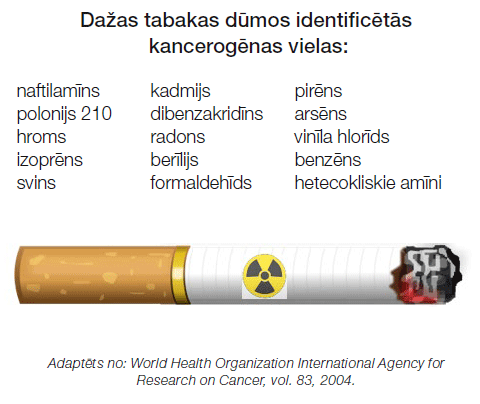

Smēķēšana bojā šūnas, kas izklāj elpceļus un plaušas. Jau mirklī, kad jūs ieelpojat cigarešu dūmus (kas satur vairākas vēzi izraisošas vielas – kancerogēnus), nekavējoties sākas pārmaiņas plaušu audos. Sākumā organisms ir spējīgs tikt galā ar šūnu bojājumiem un salabot tos, taču ar katru nākamo reizi bojājums kļūst nopietnāks, izraisot pārmaiņas šūnās un veicinot to pārtapšanu par vēža šūnām. Vēzis var attīstīties gan aktīviem, gan pasīviem smēķētājiem. Svarīgi, ka, atmetot smēķēšanu pat pēc vairāku gadu smēķēšanas stāža, jūs varat būtiski samazināt plaušu vēža attīstības risku. Diemžēl izvairīšanās no smēķēšanas negarantē, ka cilvēks nesaslims, un šādos gadījumos ir grūtāk skaidri identificēt slimības iemeslu, kas varētu būt iedzimtība, azbesta vai smago metālu ietekme.

Tabakas produktu smēķēšana ir galvenais plaušu vēža riska faktors. Vairāk kā 80% plaušu vēža slimnieku ir esoši vai bijušie smēķētāji. Tāpēc ir ļoti svarīgi smēķēšanu neuzsākt vispār vai to pēc iespējas ātrāk atmest. Tabakas dūmos ir identificētas vismaz 50 potenciāli kancerogēnas vielas, kuras skar elpceļus izklājošas šūnas. Dažas no šīm vielām ir radioaktīvas, dažas ir indes.

Smēķēšanas stāžu rēķina paku gados, t.i. cik gadus pacients smēķējis pa 1 paciņai dienā. Smēķēšanas stāžs > 20 paku gadiem ir saistīts ar nozīmīgi paaugstinātu plaušu vēža risku, īpaši pēc 50 gadu vecuma. Smēķējot cigarešu paciņu dienā plaušu vēža risks palielinās līdz pat 30 reizēm salīdzinot ar nesmēķētājiem! Par nekad nesmēķējušu uzskata cilvēku, kurš dzīves laikā izsmēķēja mazāk par 100 cigaretēm. Pasīvā smēķēšana ir tabakas produktu ieelpošana no gaisa blakus smēķētājam. Tas nozīmē, ka pasīvais smēķētājs ieelpo ar tabakas dūmiem arī kancerogēnus, kas paaugstina risku saslimt ar plaušu vēzi līdz pat 30%. Jo ilgāka ir pasīvās smēķēšanas pieredze, jo lielāks ir plaušu vēža attīstības risks. Ļoti svarīgi pasargāt no pasīvās smēķēšanas bērnus! Alternatīva tabakas smēķēšanai ir “tvaikošana”, veipošana, jeb elektroniskās cigaretes. Šis smēķēšanas veids balstās uz to, ka ierīcē tiek uzsildīts šķidrums ar augu izcelsmes glicerīnu, tas rada tvaikus un ar tvaiku elpceļos tiek nogādāts smēķēšanas ierīcē esošais nikotīns. Pagaidām nav datu par šī smēķēšanas veida tiešo saistību ar plaušu vēzi un ilgtermiņa efektiem, taču ir zināms, ka tvaikošana izraisa nopietnu